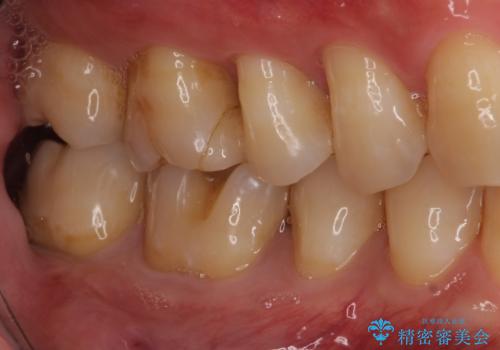

セラミックが欠けるほど強い力がかかっているということは、ご自身の歯も割れている(小さいヒビ等も含む)可能性があります。拡大鏡でしっかり見ながら治療します。

咬む力が強いため、このままでは何度もセラミックとご自身の歯を割る可能性就寝時マウスピースの使用をご提案しました。患者様には、大変満足して頂きました。